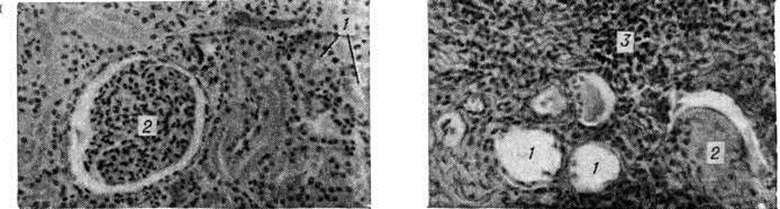

Травматический Гидронефроз развивается вследствие сдавления мочеточника гематомой в результате его повреждения (огнестрельное ранение, разрыв при операциях) с последующим образованием спаек или стриктуры. При всех видах механического затруднения оттока мочи в возникновении Гидронефроз имеют значение и функциональные нарушения лоханочно-мочеточникого сегмента. ПатогенезПри Гидронефроз процесс секреции и реабсорбции мочи сохраняется, но имеет место некоторое отставание эвакуации мочи из лоханки, что обусловливает накопление содержимого и повышение давления в ней. Это даёт право гидронефротическую почку почти всегда считать функционирующим органом, что доказано радиоизотопными исследованиями — из закупоренной почечной лоханки в ток крови реабсорбируются изотопы натрия, йода, коллоидного золота [Перски (L. Persky) с соавторами, 1955]. В начальных стадиях гидронефротической трансформации при стазе мочи в лоханке наступает гипертрофия мускулатуры лоханки и чашечек. Постепенно нарастающая гипертрофия спиральной мускулатуры чашечек приводит к резко повышенному давлению мочи на сосочек и форникальную зону. Это создаёт трудности нормальному выделению мочи из сосочков в почечную лоханку, в некоторой степени компенсируемые уменьшенной секрецией мочи. Однако это относительное равновесие функции почки продолжается недолго. Рабочая гипертрофия мышечных элементов чашечек и лоханки сменяется их истончением и разволокнением, что нарушает отток мочи и приводит к дилатации почечной лоханки и чашечек с последующей атрофией сосочков и почечной паренхимы. Одним из важных моментов в возникновении Гидронефроз является задержка выведения мочи из функционально деятельных участков почки, что наблюдается даже при кратковременных повышениях внутрилоханочного давления. Высокое давление в почечной лоханке вызывается не только поступающей в неё мочой, но и чрезмерным сокращением мускулатуры чашечек, особенно форникального и чашечного сфинктеров. А. Я. Пытель (1959) придаёт большое значение мышечной системе чашечек и лоханки в оттоке мочи по собирательным канальцам и межтканевой жидкости. Уже спустя 24 часа после закрытия просвета мочеточника начинается атрофия почечных пирамид вследствие сдавления их трансфорникальным отёком, сосочки постепенно уплощаются. Через 6—10 дней атрофия пирамид достигает большей степени, сосочки становятся вогнутыми. Наряду с деформацией форниксов происходит расширение просвета собирательных канальцев, облегчающее поступление мочи из лоханки в тубулярную систему. При полной окклюзии мочеточника происходят множественные форникальные разрывы, в результате чего создаётся рефлюкс мочи в почечное интерстициальное пространство, в кровеносную или лимфатические, систему. Повышенное внутри-паренхиматозное давление нарушает кровоток в сосудах мозгового вещества почки, что приводит к атрофии пирамид. Сдвиги кровообращения в кортикальных и медуллярных капиллярах сопровождаются изменениями кровообращения в паренхиме и тканевом обмене, а также кислородным голоданием, способствующими тотальной атрофии коркового вещества почки. Кьяудано (М. Chiaudano, 1958), Н. А. Лопаткин (1960) полагают, что гидронефротическая трансформация протекает по двум фазам: в первой атрофируется мозговое вещество, во второй — корковое. Наступающие изменения кровеносной системы почки, чашечек постепенно приводят к тотальному Гидронефроз Большая роль в патогенезе Гидронефроз принадлежит нарушениям эластической мембраны внутрипочечных сосудов, а также лимфатические, системе. Вследствие повышения проницаемости капилляров развивается отёк и компенсаторное расширение лимфатические, сосудов, участвующих в резорбции мочи, с последующим нарушением лимфообращения. В терминальной стадии гидронефротической трансформации после атрофии форниксов резорбция гломерулярного фильтрата происходит путём тубуловенозного рефлюкса. Таким образом, лоханочно-почечный рефлюкс (смотри) имеет безусловное значение при развитии Гидронефроз. Эти компенсаторные механизмы приводят к снижению давления мочи и способствуют сохранению почечной секреции на длительное время. Патологическая анатомия. Морфологически изменения при Гидронефроз зависят в первую очередь от стадии болезни. В начальных стадиях почка (независимо от внутри- или внепочечной локализации лоханки) мало отличается от здоровой. В основном патологический изменения выражены в чашечках и лоханке. Под действием повышенного внутрилоханочного давления увеличивается ёмкость чашечек и в значительной степени изменяется их конфигурация — они становятся круглыми, шейка их укорачивается и увеличивается в поперечном размере. Подобная картина чаще наблюдается при внутрипочечном расположении лоханки; она носит название гидрокаликоз (расширение одной или нескольких чашечек). Одновременно с увеличением размеров чашечек нарастает ёмкость лоханки; это происходит быстрее при внепочечном её расположении. Таким образом, к гидрокаликозу присоединяется и пиелоэктазия, а при низких локализациях препятствий развивается гидроуретеронефроз. Стенка лоханки постепенно истончается вследствие прогрессирующей атрофии гладких мышечных волокон и замены их соединительной тканью; погибают нервные окончания; облитерируются кровеносные и лимфатические, сосуды лоханки. Существует параллелизм между длительностью существования препятствия оттоку мочи и степенью нарушения нервно-мышечного тонуса лоханки. В терминальной стадии Гидронефроз лоханка представляет дряблый тонкостенный мешок, стенки которого в основном состоят из грубоволокнистой соединительной ткани. Прогрессивно растягивающаяся лоханка оттесняет почечную паренхиму к периферии, сдавливает форникальные вены и артериолы. В почечной паренхиме постепенно развиваются явления атрофии и склероза (рисунок 2), позже почка превращается в соединительнотканный мешок с отдельными остатками нормальной ткани. Наблюдаются и различные изменения сосудов почки — артерии становятся извитыми, удлинёнными, расширенными. Артериография удалённых почек и прижизненная серийная ангиография позволили обнаружить сужения магистральной почечной артерии, облитерацию и запустевание её ветвей. При этом, чем глубже выражена атрофия почки, тем уже их просвет, тем дальше отстоят ветви одна от другой (Н. A. Лoпаткин, 1961). В этой стадии Гидронефроз почка бывает резко увеличена в размерах, корковый слой её очень тонкий (цветной рисунок 1 и 2). Клиническая картинаВ течении гидронефроза принято выделять три стадии: I — начальную, II — раннюю, III — терминальную. Гидронефроз часто развивается бессимптомно и проявляется при вспышке инфекции, травме или случайно обнаруживается при пальпации брюшной полости. Симптомов, характерных только для Гидронефроз, нет. Наиболее часты боли в поясничной области разной интенсивности, постоянного ноющего характера, а в ранней стадии — в виде приступов почечной колики. Приступы сопровождаются тошнотой, рвотой и вздутием живота. Часто больные отмечают уменьшение количества мочи перед приступами и во время них и увеличение после разрешения приступа. В далеко зашедших стадиях Гидронефроз острые боли не характерны. Повышение температуры во время приступов боли может быть только при инфицированном Гидронефроз, что объясняется возникновением пиеловенозного рефлюкса. Важным симптомом при большом Гидронефроз является прощупываемое в подреберье опухолевидное образование. Гематурия (микро- и макроскопическая) — нередкий, иногда единственный симптом. В терминальной стадии заболевания функция почки резко нарушается. Явления почечной недостаточности появляются главным образом при двустороннем процессе. Осложнения — присоединение инфекции, образование вторичных камней и разрыв гидронефротического мешка при травме. ДиагнозПальпацией удаётся распознать Гидронефроз лишь в поздних стадиях. Хромоцистоскопия (смотри) является вспомогательным методом, позволяющим заподозрить Гидронефроз и судить о секреторной функции почечной паренхимы и о моторной функции лоханки и мочеточника. При Гидронефроз индигокармин на больной стороне выделяется с запозданием и вялой, слабо окрашенной струёй или вовсе не выделяется. Для более точного суждения о секреторной функции почки рекомендуется хромоцистоскопия с катетеризацией мочеточника, что даёт возможность судить о его проходимости и локализации в нем препятствия, о наличии и количестве остаточной мочи в лоханке; кроме того, представляет возможность получить мочу раздельно из каждой почки. Основная роль в диагностике Гидронефроз принадлежит рентгенологическое методам. Обзорная рентгенография позволяет определить размеры почки и иногда обнаружить камни. На экскреторной урограмме, произведённой через 10 минут после введения контрастного вещества в вену, выявляются слабо очерченные тени полостей почки вследствие большого разведения препарата остаточной мочой, содержавшейся в лоханке. Затем происходит накопление контрастного вещества (вследствие нарушения эвакуации мочи), и снимок (через 20 минут после первого) показывает изображение расширенных чашечек и лоханки. При значительных изменениях паренхимы накопление контрастного вещества замедляется и становится заметным на урограмме лишь через 1 — 2 часа после введения его в вену, а при резкой атрофии почки препарат не выделяется вовсе; в не которых случаях это может зависеть и от угнетения деятельности почки вследствие острой обтурации мочевых путей. Изображения на урограммах при Гидронефроз имеют разнообразную форму — от умеренной пиелоэктазии до большой круглой или овальной полости с резко расширенными чашечками; полости с чёткими ровными краями, что отличает Гидронефроз от пионефроза. На уретерограмме видны зоны стриктур, перегибов, атоничные мочеточники, а также обтекаемые контрастным веществом препятствия в нем, например, камни, опухоль. Поперечный перерыв тени в области лоханочно-мочеточникового сегмента характерен для клапана, добавочного сосуда (рисунок 3). Ретроградную пиелографию (смотри) при больших Гидронефроз в связи с опасностью тяжёлых осложнений целесообразно производить в день операции. После пиелографии в этих случаях необходимо извлекать катетер через 30—60 минут после опорожнения лоханки от мочи. В других случаях дренирование лоханки обеспечивает отток мочи и предотвращает возможность осложнений. Анализ мочи, раздельно взятой из почек, и бактериологических исследование её с определением чувствительности микрофлоры к антибиотикам при инфицированном Гидронефроз дополняют клинической, диагностику. Селективную артериографию (рисунок 4) для диагностики Гидронефроз производят сравнительно редко с целью уточнения стадии процесса изучения сосудистого рисунка почки, а также выявления добавочного сосуда (смотри Почечная ангиография). Изредка применяют чрескожную пункционную антеградную пиелографию (рисунок 5). Радиоизотопная ренография существенно дополняет рентгено л. исследование, особенно при двустороннем Гидронефроз, когда удаётся выявить сторону наибольшего поражения (смотри Ренография радиоизотопная). Дифференциальный диагноз проводят с различными заболеваниями почек и органов брюшной полости. При Гидронефроз, протекающем с болевым синдромом, следует дифференцировать Гидронефроз с нефролитиазом (смотри Мочекаменная болезнь), нефроптозом (смотри). Обзорная рентгенография или пневмопиелография подтверждает или исключает нефролитиаз. При нефроптозе боли возникают главным образом при движениях и физических напряжениях и быстро стихают в горизонтальном положении. Если при пальпации обнаружена опухоль, необходимо решить, расположена ли она в забрюшинном пространстве или в брюшной полости. Это достигается урографией (смотри) и введением газа в забрюшинное пространство (смотри Пневморетроперитонеум). В отличие от Гидронефроз, опухоль почки малоподвижна, плотна, бугриста. На пиелограмме характерны деформация лоханки или «ампутация» чашечек (дефекты наполнения). При поликистозе обе почки увеличены, бугристы; отмечаются явления почечной недостаточности; типична и пиелограмма — удлинённая лоханка и вытянутые в виде полулуний чашечки. Солитарной кисте почки свойственно сдавление полостей чашечек и лоханки, видимое на пиелограмме. Лечение должно быть направлено на устранение причины, вызвавшей развитие Гидронефроз, и сохранение почки. Среди различных методов хирургического лечения наиболее распространены пластические.